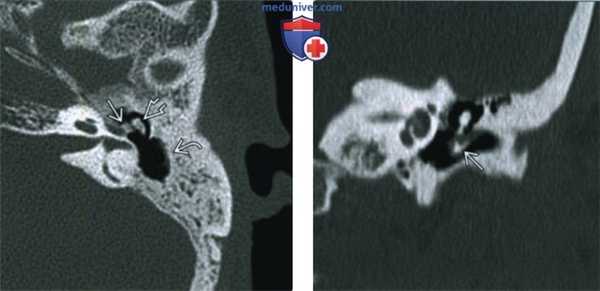

(Слева) При аксиальной КТ в костном окне определяется локальный участок оссифицирующего тимпаносклероза сразу же за слуховыми косточками в медиальной стенке эпитимпанум. Также обратите внимание на слияние наковальне-молоточкового сустава. В сосцевидном отростке присутствует лишь сосцевидная пещера.

(Справа) При корональной КТ в костном окне определяется утолщение барабанной перепонки с вытянутым кальцинатом вдоль ее поверхности. Обызвествления при тимпаносклерозе могут обнаруживаться в связках, сухожилиях, слуховых косточках, или в барабанной перепонке, как в этом случае.